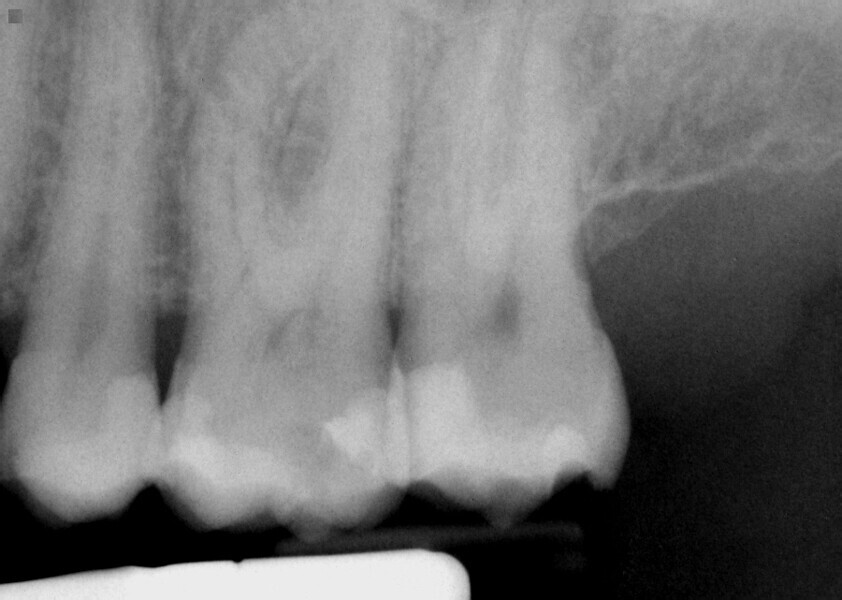

Fig. 16: Patient presented with percussion and hot sensitivity on the lower first molar that she reported was increasing over the past week.

Fig. 17: Instrumentation was performed with ExactTaperH DC files and single cone obturation with Bioceramic Root Canal sealer completing the endodontic treatment preserving the cervical tooth structure during the treatment.